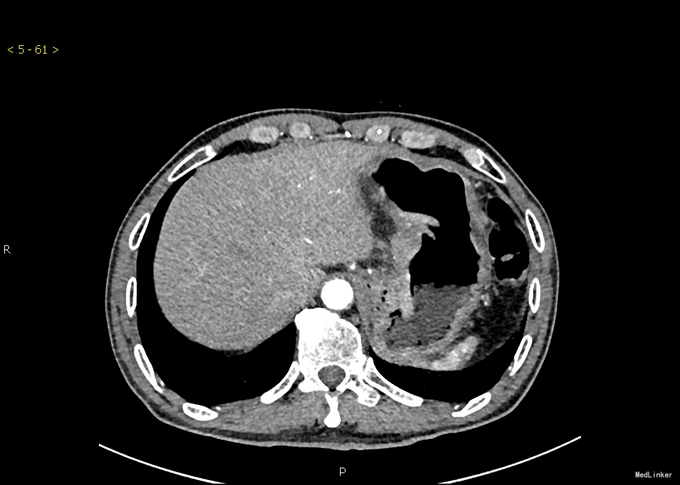

查体:无特殊。 辅查:腹增强CT:CT科室讨论:胃体部小弯侧胃壁弥漫性增厚,考虑胃癌并腹腔、腹膜后淋巴结转移可能性大,建议胃镜检查。 PET/CT提示:1.胃体小弯侧胃壁溃疡及胃周、肝门部及腹膜后多发肿大淋巴结糖代谢不同程度增高,考虑胃癌并多发淋巴结转移;其余部位未见恶性肿瘤代谢影像。 胃镜示:贲门、胃底、胃体:齿状线欠清,可见一巨大浸润肿物,从贲门延至胃底胃体,表面凹凸不平、溃烂,质脆触易出血,予活检。病理结果:(胃)分化差的癌,考虑为混合性腺神经内分泌癌。